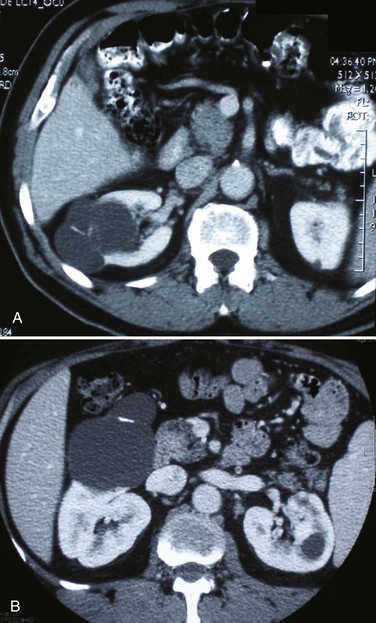

Category III lesions are more complex renal cysts that cannot be confidently distinguished from malignant neoplasms (Kausik, 2002; Israel and Bosniak, 2005). The radiographic features include thickened irregular or smooth walls or septa in which measurable enhancement can be observed (Fig. 49–7). In the absence of a mitigating factor such as renal trauma or infection, surgical exploration is usually indicated in healthy patients. About 50% of these lesions are malignant; the remainder prove to be benign multiloculated, hemorrhagic, or densely calcified cysts (see Table 49–2). Fine-needle aspiration of complex cysts is rarely performed because of concern about sampling error and tumor cell spillage.

Figure 49–7 Bosniak class III cysts. A, CT scan shows complex right renal cyst with thick and irregular septa and inhomogeneous character. B, CT scan shows somewhat thick-walled, complex left renal cyst also exhibiting irregular calcification and moderate heterogeneity.

(Courtesy of Dr. Terrence Demos, Maywood, IL.)